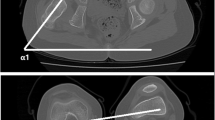

Radiographic measurements were performed using our digital PACs system (iSite v3.6; Philips Healthcare, Andover, MA, USA) by two experienced clinicians (JC, JAE) on preoperative films. The AP radiograph was used to obtain the alpha neck-shaft angle (Fig. 2) and the crosstable lateral radiograph was used to measure the beta neck-shaft angle (Fig. 3). The initial reader (JC) performed all reads from preoperative films, but may have visualized the stem in the PACS system. Similarly, a second, experienced clinician (JAE) then read the same radiographs twice (blinded to the first reads), 1 week apart, to allow for assessment of interrater and intrarater reliability and agreement. The concordance correlation coefficient (rc) and a Bland-Altman analysis were used for this analysis [2, 6]. The amount of agreement between readers for the rc was classified as minimal, < 0.2; poor, 0.2 to < 0.4; moderate, 0.4 to < 0.6; strong, 0.6 to ≤ 0.8; and almost perfect, > 0.8 [10]. There was strong agreement between the two clinicians when measuring the alpha neck-shaft angle and the beta neck-shaft angle (Table 2). Furthermore, the intrarater agreement also demonstrated almost perfect agreement between reads (Table 3). Thus, the measurements from the first reader were used in this analysis.

Based on these measurements, we then calculated the patient femoral anteversion based on the formula presented by Ogata and Goldsand [9] (tanθ = tanβ/tanα). In their original publication, they described α (Fig. 2) and β (Fig. 3) as supplementary angles to what we calculated as neck-shaft angles, which we then corrected for in our equations. We used Microsoft Excel (Microsoft Inc, Redmond, WA, USA) to perform the calculations as follows:

Equation 1: 180°- AP neck-shaft angle = α

Equation 2: 180°- lateral neck-shaft angle = β

Equation 3: “θ = TAN (RADIANS [β])/TAN (RADIANS [α])”

Equation 4: “Anteversion = DEGREES(ATAN [θ])